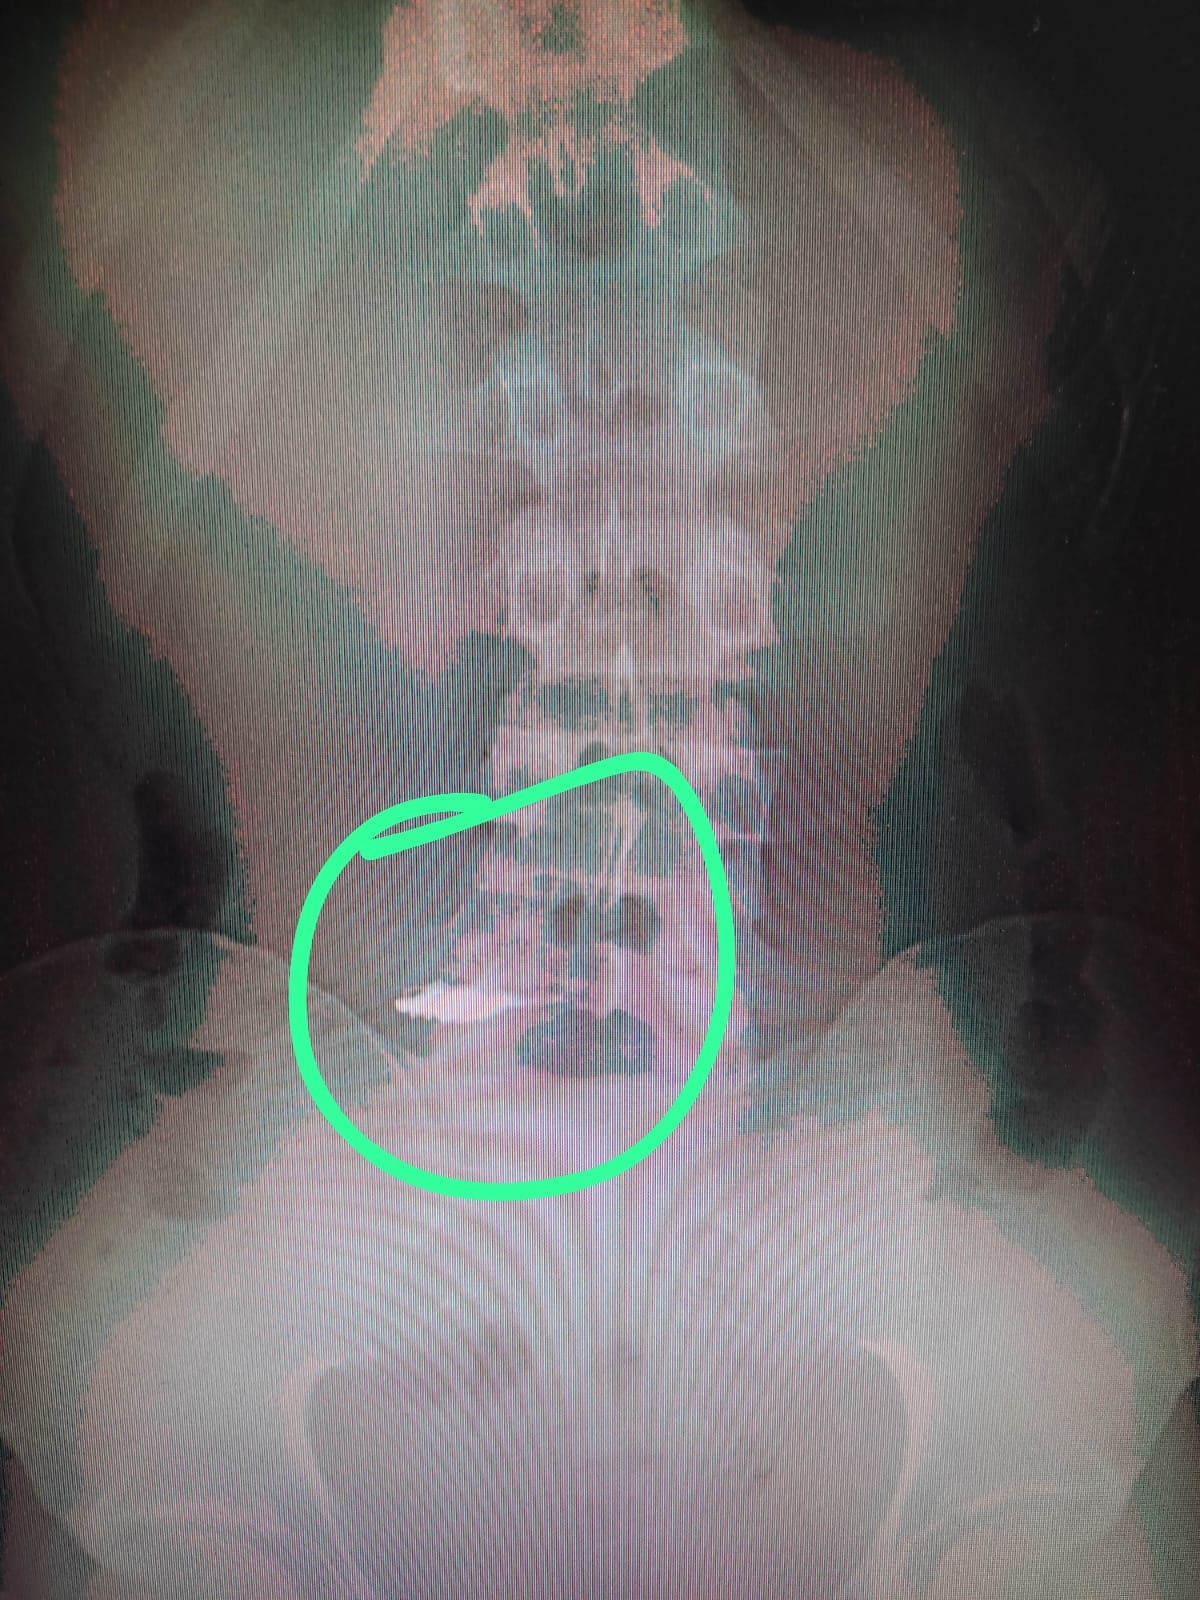

Posteriormente, quando levado para a Unidade de Pronto Atendimento (UPA) dos Barris, as correntes foram localizadas por meio de um raio-x, após o suspeito ter engolido os objetos.

As correntes foram localizadas por meio de um raio-x. Foto: Reprodução